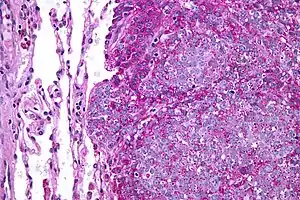

Ewing sarcoma is a small-blue-round-cell tumor that typically has a clear cytoplasm on H&E staining, due to glycogen. The presence of the glycogen can be demonstrated with positive PAS staining and negative PAS diastase staining. The characteristic immunostain is CD99, which diffusely marks the cell membrane. However, as CD99 is not specific for Ewing sarcoma, several auxiliary immunohistochemical markers can be employed to support the histological diagnosis.[18] Morphologic and immunohistochemical findings are corroborated with an associated chromosomal translocation, of which several occur. The most common translocation, present in about 90% of Ewing sarcoma cases, is t(11;22)(q24;q12),[19][20] which generates an aberrant transcription factor through fusion of the EWSR1 gene with the FLI1 gene.[21]

The pathologic differential diagnosis is the grouping of small-blue-round-cell tumors, which includes lymphoma, alveolar rhabdomyosarcoma, and desmoplastic small round cell tumor, among others.